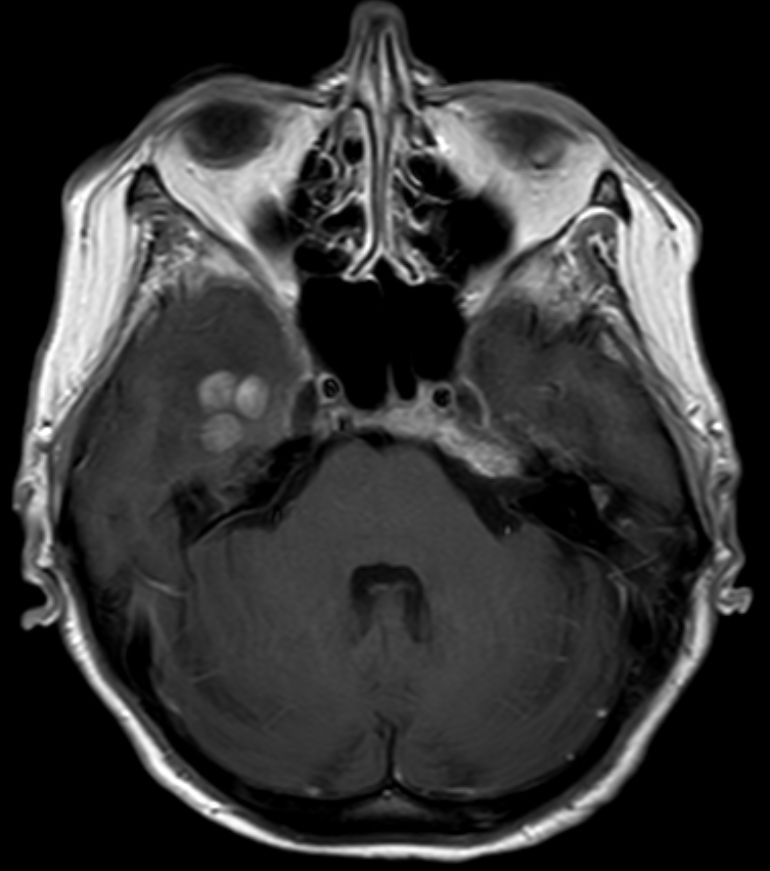

| Schädelbasis | 62-jährige Frau, bei der vor 2 Monaten ein Plattenepithelkarzinom der Zervix FIGO IIIB mit Radiochemotherapie behandelt wurde. Die Uterusgröße hatte von 13 auf 6 cm abgenommen. Jetzt Aufnahme mit der Diagnose Apoplex. | |||

An der Basalfläche des rechten Temporallappens KM - aufnehmende RF.![]() |

![]() | |||